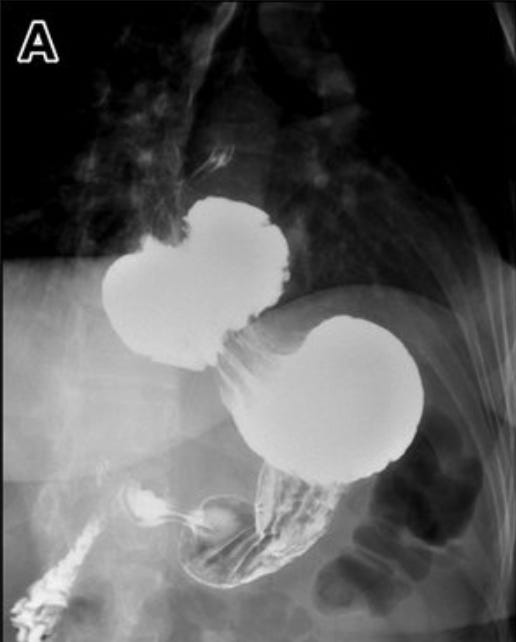

A barium swallow can be useful too…particularly for characterising para-oesophageal hernias and assessing the stomach’s position relative to the diaphragm.

For complex cases, high-resolution manometry offers the most accurate assessment. A meta-analysis of over 5,000 patients found it outperformed both endoscopy and barium studies for diagnostic precision.